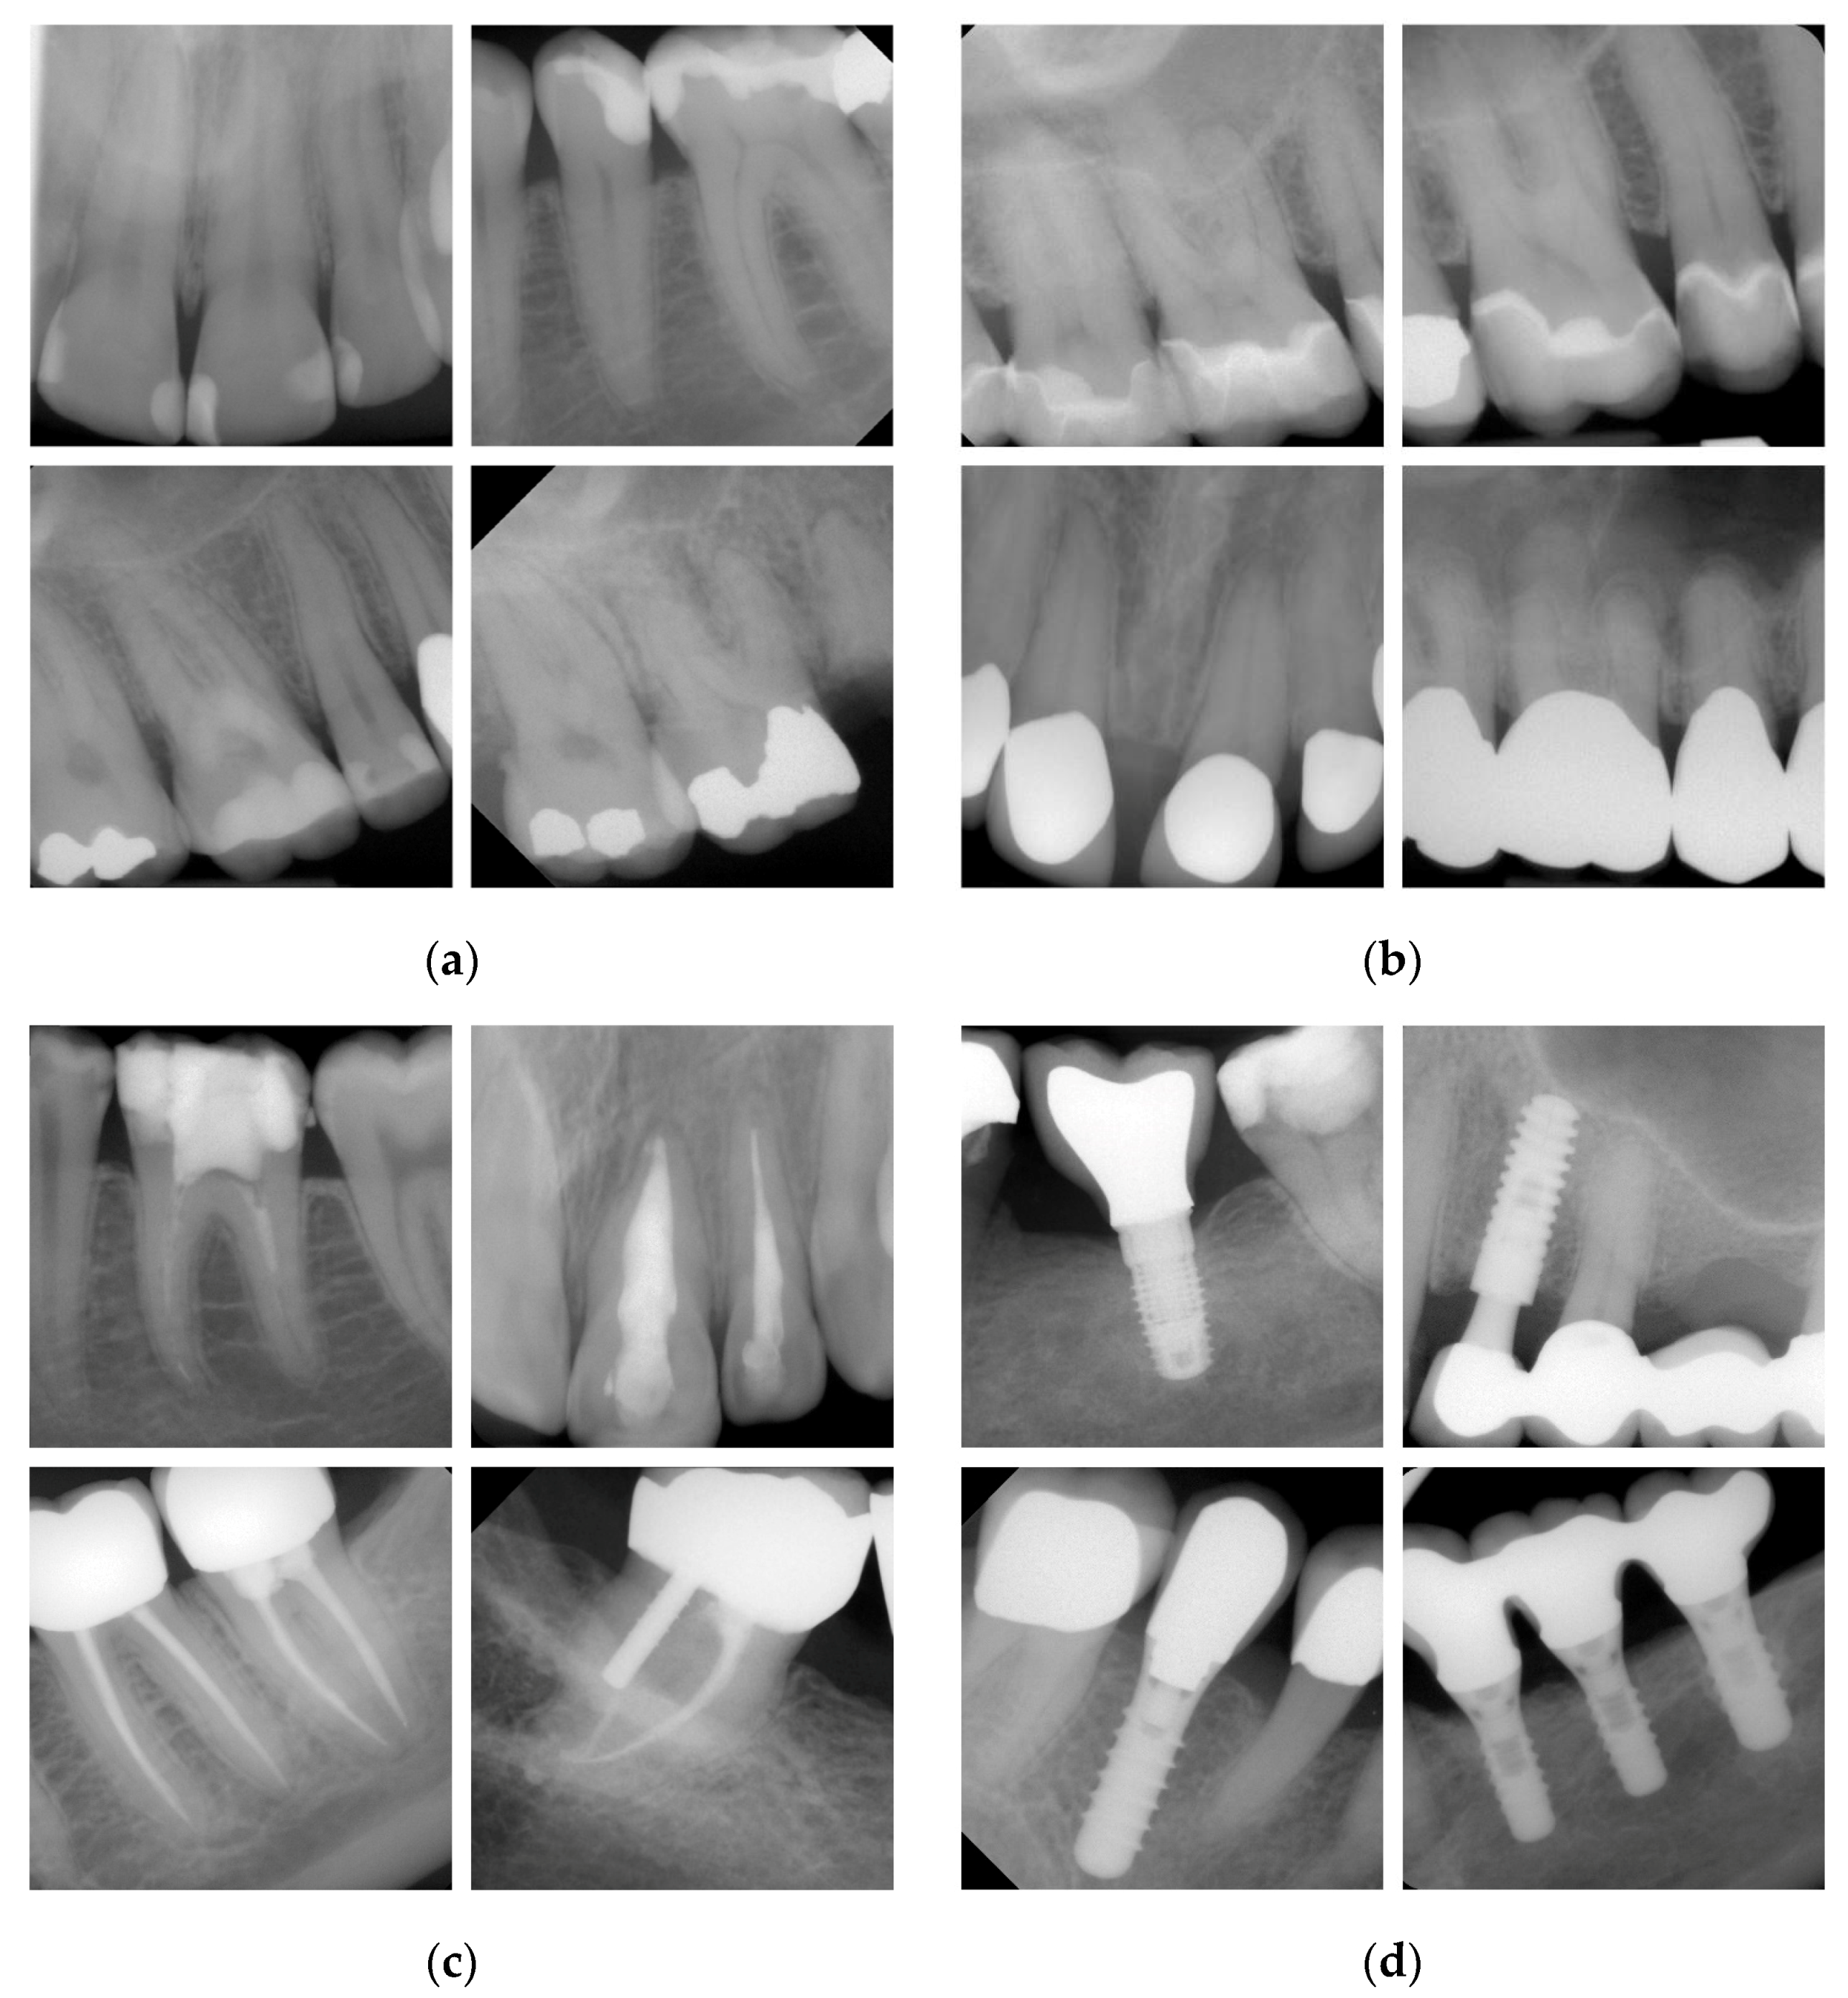

2.2. Set of Dental Radiographs